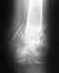

Покажите хотя бы наиболее свежие рентгенограммы бедра на протяжении.